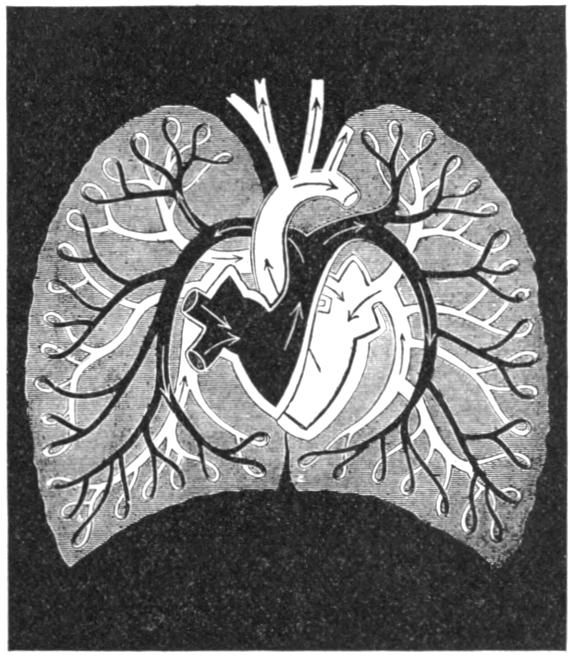

| V. | The Circulation | H 51 |